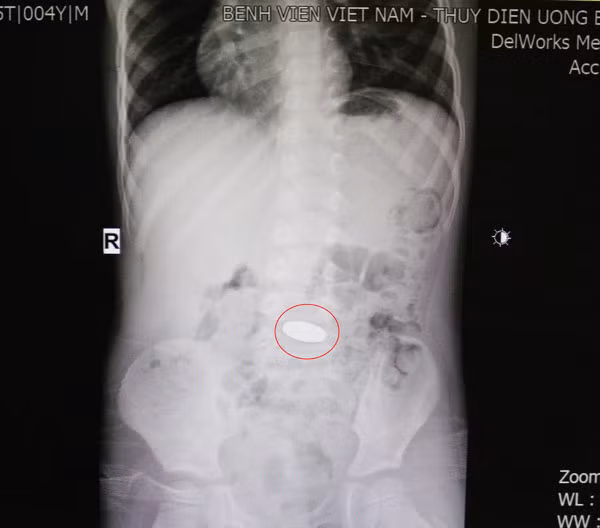

Qua chụp phim X-quang ổ bụng, các bác sĩ phát hiện đồng xu đã ở dạ dày nên tiếp tục theo dõi cho trẻ.

Theo BsCKII. Nguyễn Thị Ngọc Điệp - Trưởng khoa Nhi cho biết trường hợp bệnh nhi khi nhập viện, đồng xu đã xuống được dạ dày, không bị mắc lại ở vị trí thực quản hay đường thở. Vì vậy, trẻ tránh được nhiều biến chứng nguy hiểm.